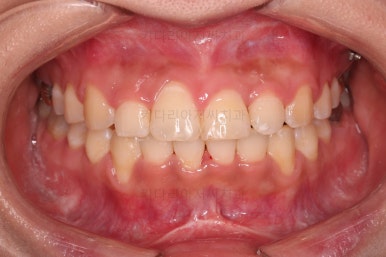

초진 시, 입 안의 모습이에요.

위아랫니가 삐뚤고 교합이 약간 맞지 않네요.

입 안만 보면 심플하게 교정하면 되겠다 싶지만, 문제는 다른 곳에 있었어요.